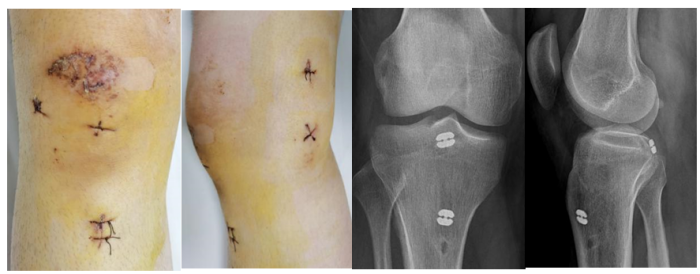

经评估,余敏团队为这两位患者实施了关节镜下微创手术,通过在膝关节周围做2个小切口,将关节镜插入关节腔内,医生可以清晰地观察到关节内的情况以进行精准的骨折块复位,并使用特殊的器械固定。这类手术创伤小、恢复快,而且不需二次手术取出内固定物,术后患者没有明显的疼痛,膝关节功能恢复理想,患者感受很好。

关节镜下微创手术切口及术后X线